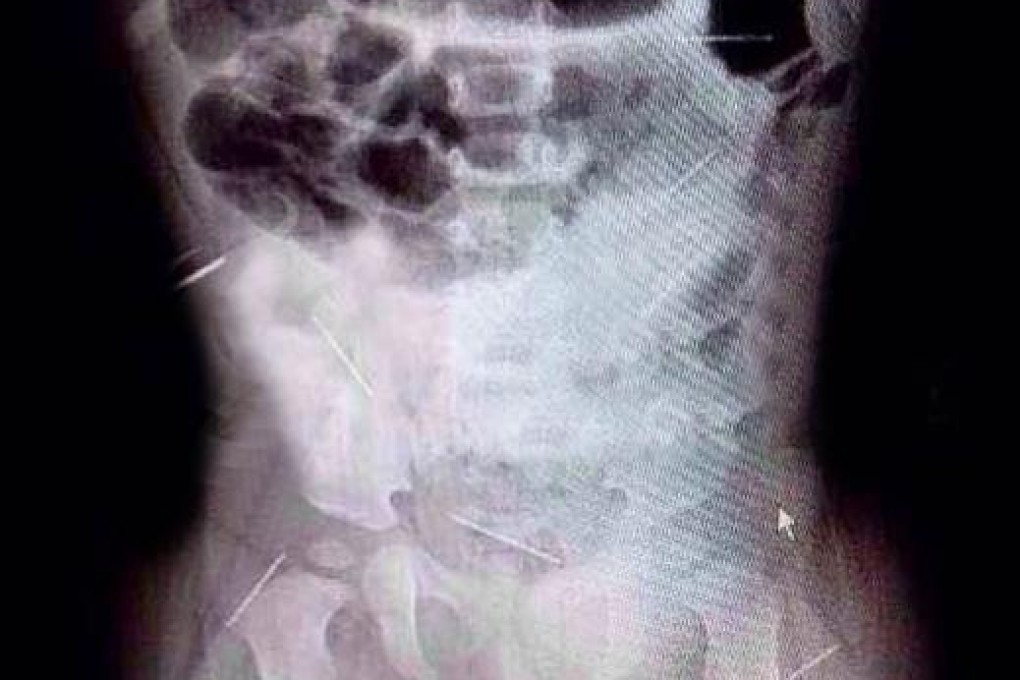

The needles were discovered after Zhang became irritable and a strange red patch appeared on her bottom. Her mother took her to hospital where X-rays revealed multiple needles had been inserted into the youngster's hip, abdomen, pelvis and ribs.